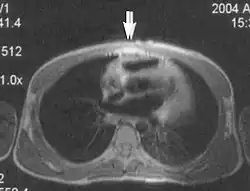

Flow can manifest as either an altered intravascular signal (flow enhancement or flow-related signal loss), or as flow-related artifacts (ghost images or spatial misregistration). Flow enhancement, also known as inflow effect, is caused by fully magnetised protons entering the imaged slice while the stationary protons have not fully regained their magnetization.[1] The fully magnetized protons yield a high signal in comparison with the rest of the surroundings. High velocity flow causes the protons entering the image to be removed from it by the time the 180-degree pulse is administered. The effect is that these protons do not contribute to the echo and are registered as a signal void or flow-related signal loss (Fig. 2).[1] Spatial misregistration manifests as displacement of an intravascular signal owing to position encoding of a voxel in the phase direction preceding frequency encoding by time TE/2.The intensity of the artifact is dependent on the signal intensity from the vessel, and is less apparent with increased TE.[1]